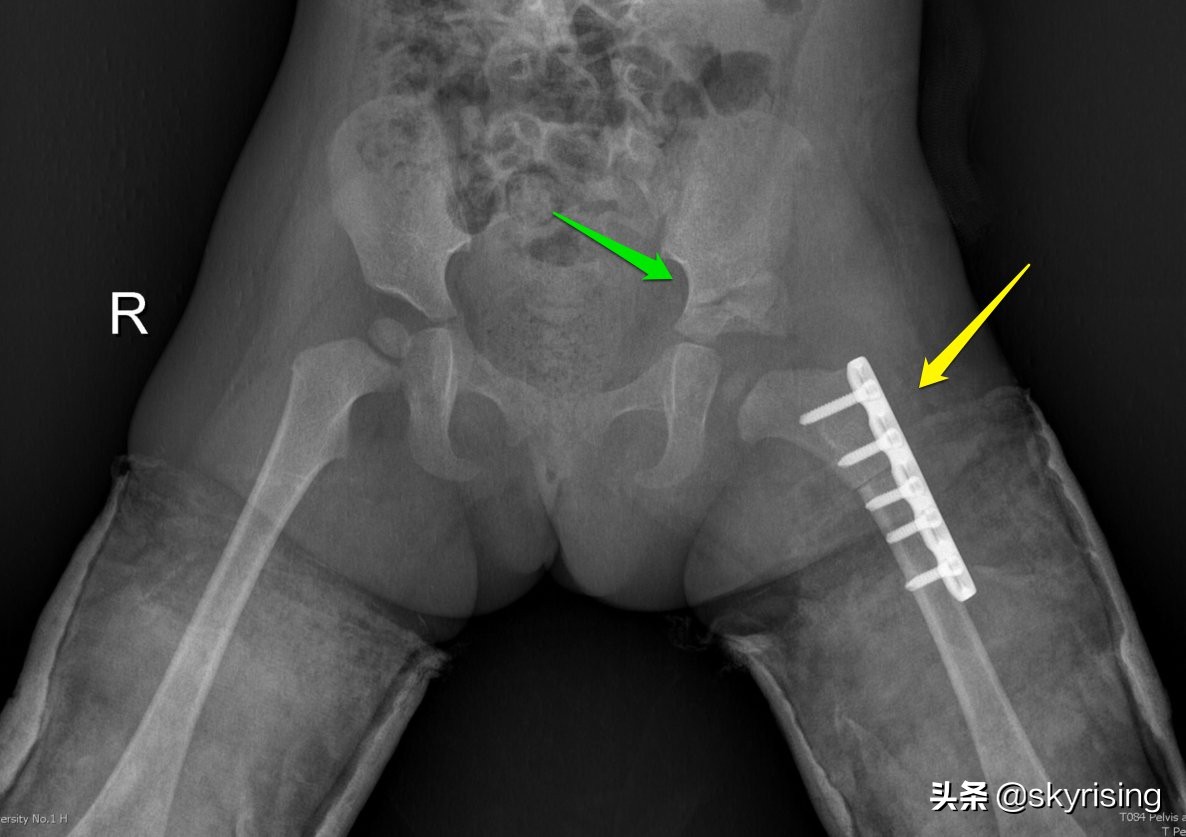

绿色箭头术后可见左侧髋臼植骨。黄色箭头左侧股骨内固定术后改变。